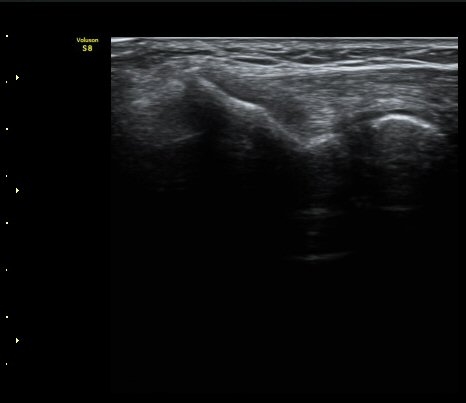

ÃÊÀ½ÆÄ °Ë»ç